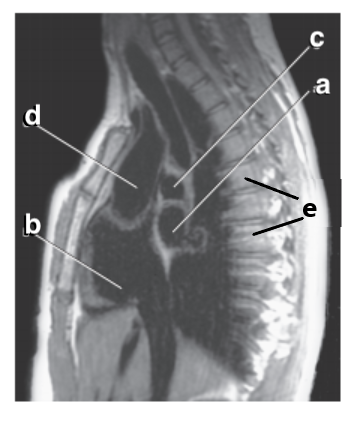

What is letter a ?

Ascending aorta

What is letter e ?

Vertebral body

What is letter c ?

Hemiazygos vein

Aortic Arch

Which letter is the descending thoracic aorta ?

e

What is letter g ?

Descending thoracic aorta

What is letter d ?

Trachea

Thoracic vertebra

What is letter f ?

Sternum